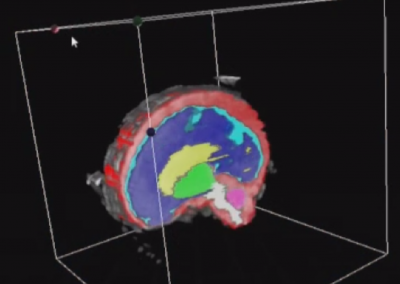

L’Université Paris Cité franchit une nouvelle étape dans le domaine de l’imagerie médicale anténatale avec l’acquisition d’un système d’Imagerie par Résonance Magnétique (IRM) 1,5T ARTIST™ de GE HealthCare. Cet équipement de pointe renforce les capacités de la Plateforme LUMIERE à l’hôpital Necker-Enfants malades, plateforme intégrée de soins, de recherche clinique et d’enseignement en imagerie médicale de la femme enceinte, du fœtus et du placenta.

Une avancée technologique majeure pour la recherche anténatale

L’acquisition de cette nouvelle IRM s’inscrit dans le cadre du protocole de recherche « LUMIERE SUR LE FETUS », dont les objectifs sont d’améliorer la prise en charge des pathologies anténatales, d’affiner leur pronostic et de contribuer à la réduction de la morbidité et de la mortalité à court, moyen et long terme. Cette acquisition a été rendue possible grâce au don exceptionnel de la Fondation LUMIERE d’un montant de 250k euros ainsi qu’au soutien de l’Université Paris Cité à hauteur de 670k euros.